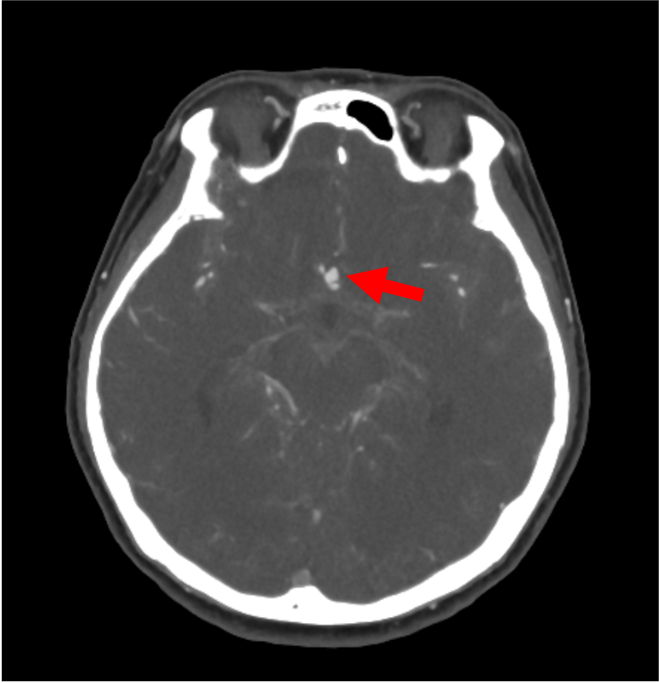

勤務中に急に意識消失し救急要請された。収縮期血圧200㎜Hgを超える高血圧も伴い、脳卒中が疑われた。頭部CTではクモ膜下腔に広範に広がる血腫を認め、くも膜下出血と診断された。前交通動脈にブレブを伴う歪な動脈瘤を認め、責任病変が疑われた。

当該疾患の診断における造影CTの役割

意識障害の原因の一つとして脳卒中があり、その中の一つにくも膜下出血が含まれる。くも膜下出血の診断は単純CTで行われる。くも膜下出血の原因の多くが脳動脈瘤の破裂である。脳動脈瘤の検索にCT angiographyが有用であり、侵襲性が少なくアクセスのしやすさからも好まれる。Volume Rendering (VR) 像は全体を俯瞰でき動脈瘤を容易に認識できることが多いが、サイズや形態により動脈瘤が分かりにくいこともあるため、元画像の確認を怠らないことが大切である。また、脈瘤破裂の他、脳動静脈奇形や脳動脈解離もくも膜下出血の原因となり、これらの有無も合わせて確認する必要がある。